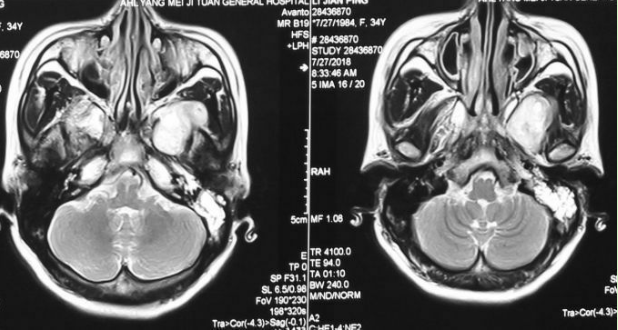

颅脑核磁示:左侧颞下窝占位。

术前增强MRI